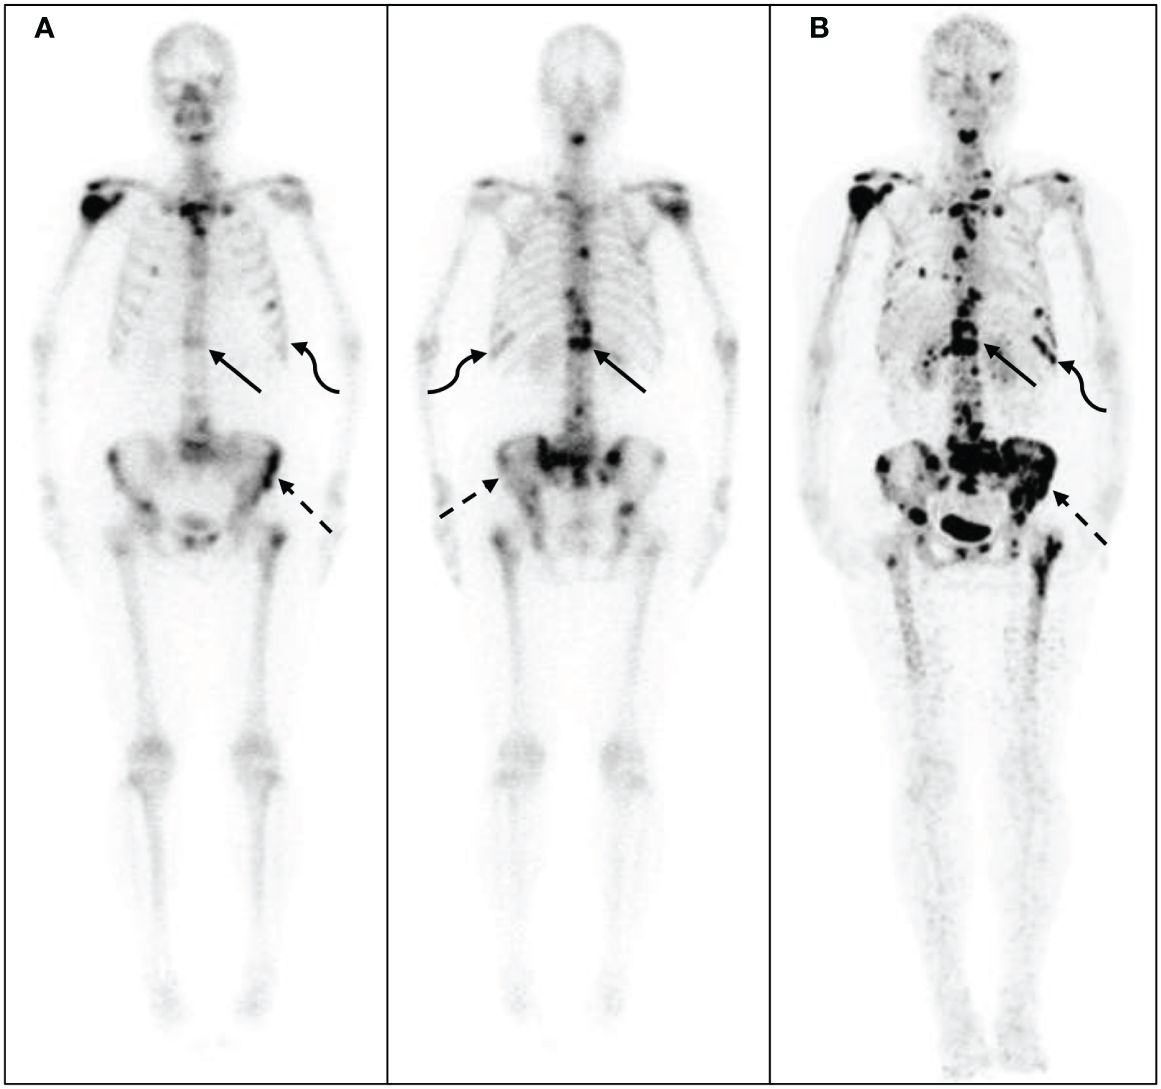

最新入荷 Imaging Features of Juvenile Xanthogranuloma of the 医学一般